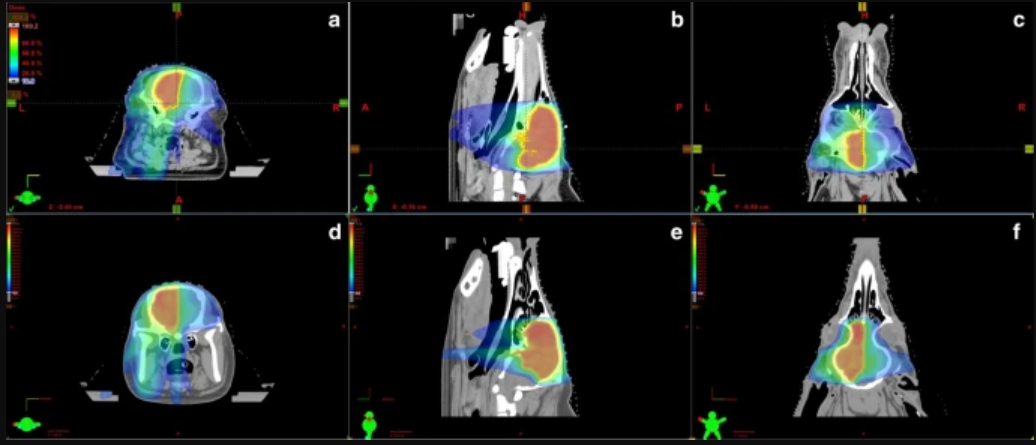

半脑放射治疗计划的质量:每头猪的放射治疗计划通过了方法中描述的质量保证。简而言之,对于PTV剂量覆盖率,93%的规定剂量至少覆盖了PTV容积的93%。图 1 规定的剂量均匀分布在PTV上,PTV边缘的剂量急剧下降。表1总结了所有猪PTV的剂量学参数。DVHs分析了PTV的最小、最大、平均和中位剂量。所有四个计划的HI、CI和GI分别为0.15–0.21、0.57–0.74和1.9–2.7。简而言之,脊髓和晶状体的剂量远低于 QUANTEC 分别为脊髓病或白内障推荐的截止剂量。关于脑干,最大剂量(D2%),尤其是P1和P2在PTV附近的一侧。然而,所有猪脑干的平均剂量都很低(3–11.3 Gy)。左右视神经,视交叉接受的剂量相对接近预期的规定剂量。左侧视神经和视交叉包含在 PTV 中,右侧视神经与 PTV 相邻。报告了 P3 和 P4 的小脑剂量学参数。最大 (D2%) 剂量在 PTV 附近被视为预期,平均剂量 (3.4 Gy) 较低。更全面地观察大脑PTV容积中未经治疗的部分,我们再次看到PTV附近的最高剂量,但平均剂量较低(规定剂量的30%至45%)。

图1、来自受试者 P1 和 P3 的治疗计划。